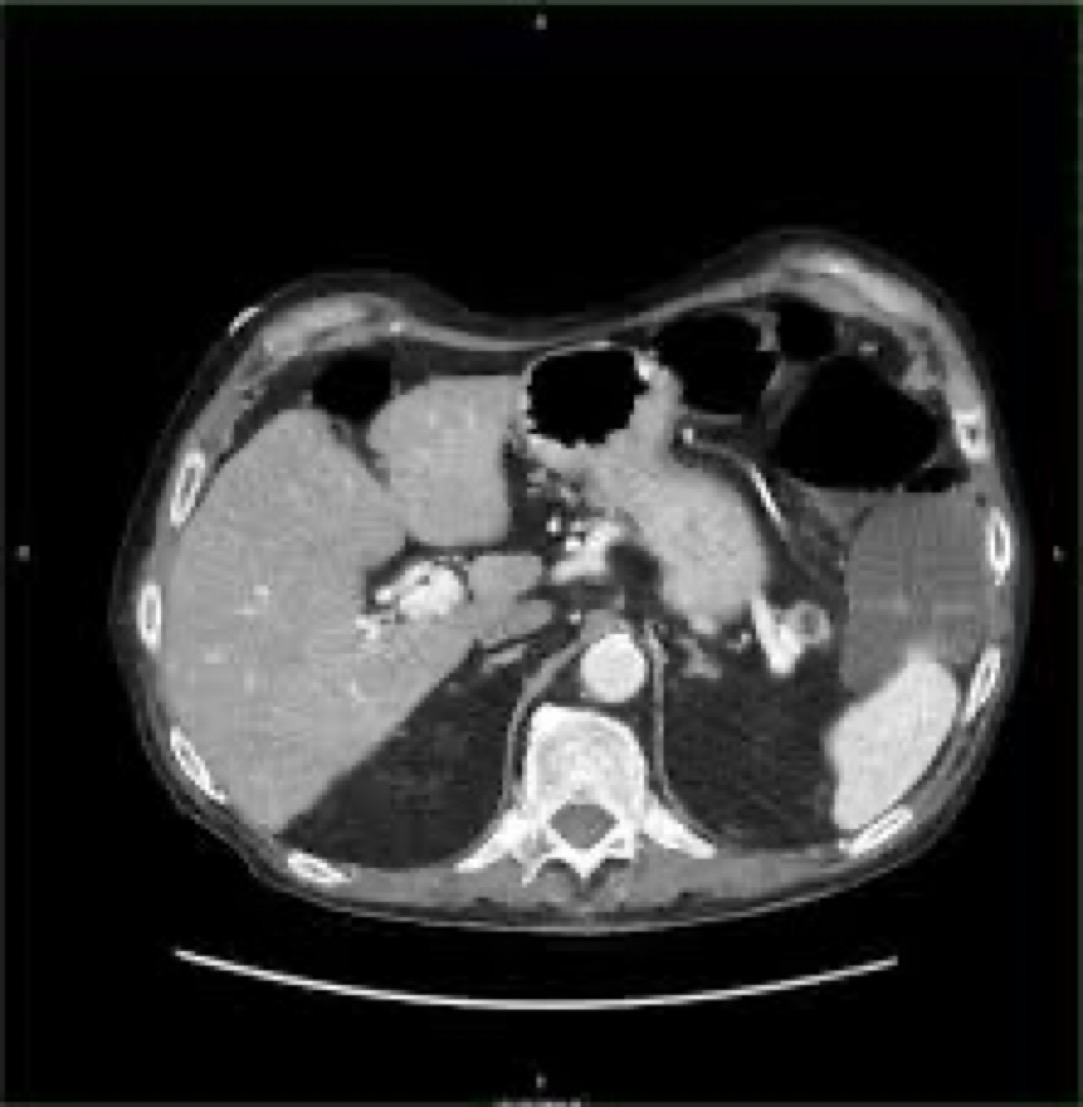

From twitter.com

Brown Hospital Medicine on Twitter "A 50yearold woman presents with Diarrhea With Flushed Face Symptoms and signs of diarrhea, excessive sweating, flushed skin and nausea or vomiting and their most common related conditions. Emotions can also cause facial flushing, referred to as blushing. Carcinoid syndrome is a group of symptoms associated with carcinoid tumours. You have acute flushing of your face, neck and chest. You have severe diarrhea that’s lasted several days. You have. Diarrhea With Flushed Face.

From www.nejm.org

Intermittent Facial Flushing and Diarrhea NEJM Diarrhea With Flushed Face Emotions can also cause facial flushing, referred to as blushing. You have severe diarrhea that’s lasted several days. Symptoms and signs of diarrhea, excessive sweating, flushed skin and nausea or vomiting and their most common related conditions. It causes the face and neck to turn red and feel warm. The most common signs and symptoms of gastroenteritis are nausea, vomiting,. Diarrhea With Flushed Face.